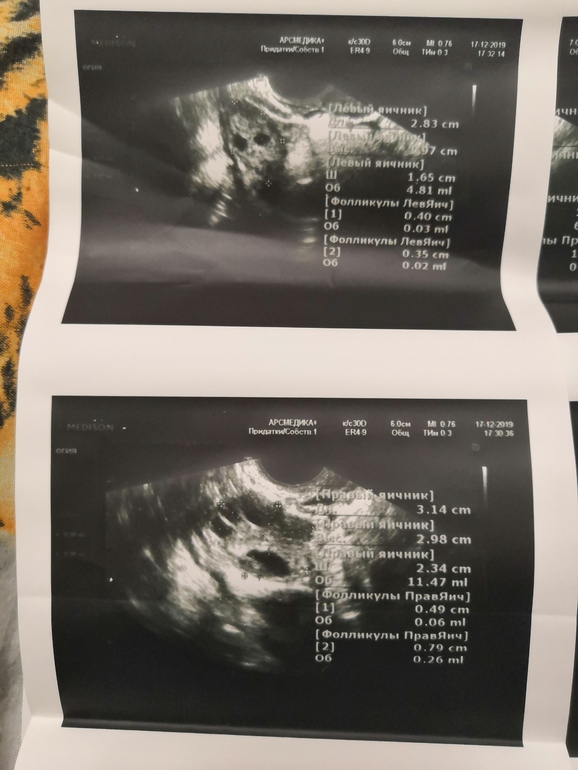

Овуляция( тесты на овуляцию)Девочки, сегодня 23 дц, была на узи. Фото ниже. Врач сказал в правом яичнике ДФ большого размера(как расшифровать размеры?) , но сказать трудно, это поздняя овуляция или все таки киста 🤷♀️🤦♀️ каковы шансы что на такой день может все же быть овуляция? И если это киста, то чем это страшно? Как её убрать потом? Я просто первый раз с таким столкнулась. 😬😬😬 Грудь стала чувствительная, месячные по календарю через 5 дней.

Я не вижу ДФ в размерах, все по 0,3-0,7 мм. ДФ это 1.8-2.3 мм. Или я спросони туплю) Обычно пишут в выписке наличие ДФ или ЖТ такого то размера.

Так вам и в левом вроде фолликулы ставят.... даа кто то сейчас кто больше понимает ответит...